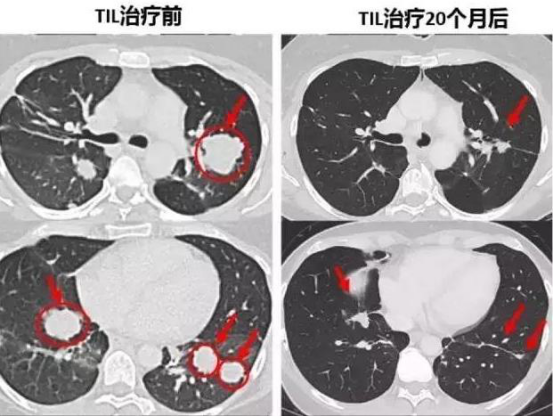

去年十一月一位46歲肺癌末期的香港婦女,經(jīng)歷三個(gè)月利用免疫細(xì)胞療法治療成功,目前身上已無腫瘤。image.png

患者Melinda Bachini,在09年確診為晚期膽管癌肝轉(zhuǎn)移的患者,術(shù)后出現(xiàn)雙肺多發(fā)轉(zhuǎn)移,她曾嘗試過毒副作用很大的化療方案,頭發(fā)掉光了,頭和腳部的神經(jīng)嚴(yán)重受損,但是病情沒有得到任何控制,甚至惡化了?;剌攦芍苤?,困擾了Melinda很久的慢性咳嗽開始緩解了。第二次回輸后,效果真的驚人!她全身腫瘤開始迅速縮小,體力恢復(fù)很快。

image.png